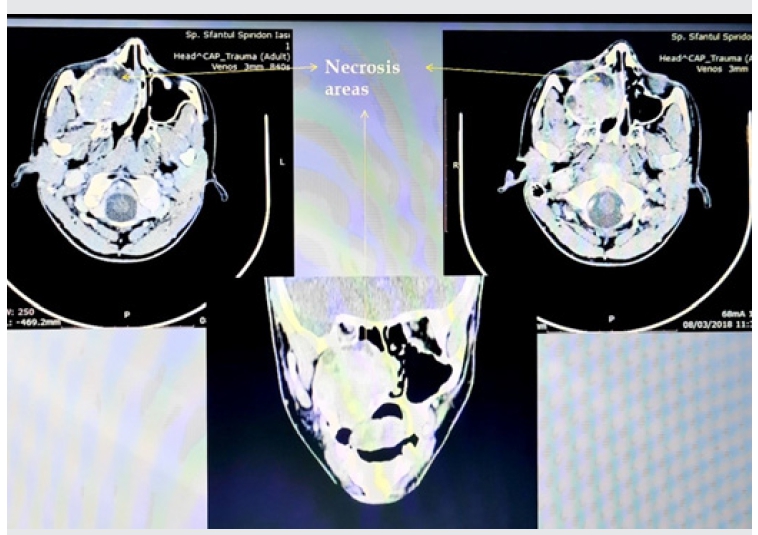

Examenul CT cranio-cerebral efectuat în data de 8.03.2018 a descris o formațiune expansivă cu diametrul de 43/52/54 mm, ce ocupă în totalitate sinusul maxilar drept, cu efect de masă asupra pereților osoși, a căror corticală o subțiază și o întrerupe segmentar.